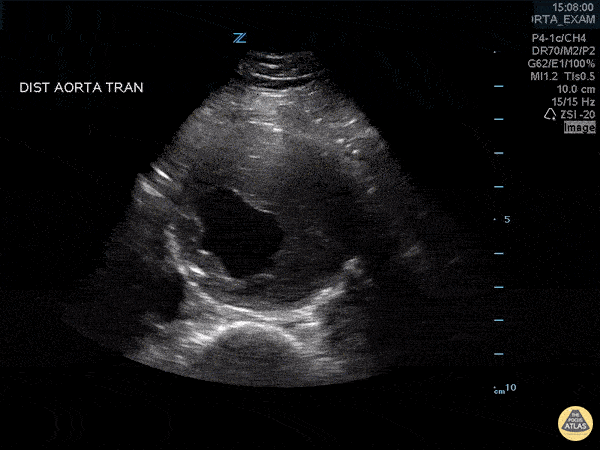

One Minute Image Review

One-Minute Image Review: High yield bite sized learning! Voice annotation of both normal and abnormal point of care ultrasound clips!